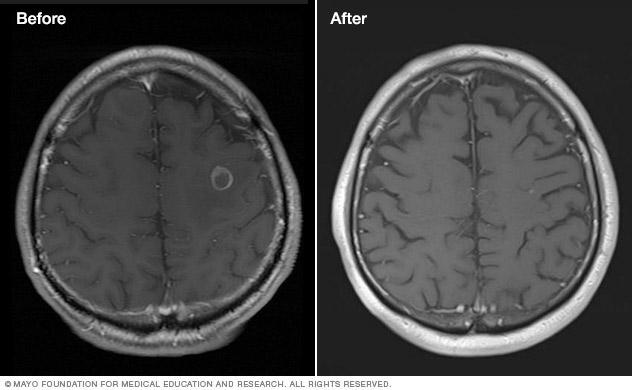

Scans of a brain tumor before and after treatment.

Brain tumor before and after Gamma Knife treatment

Malignant brain tumor before (left) and 111 months after Gamma Knife stereotactic radiosurgery (right)